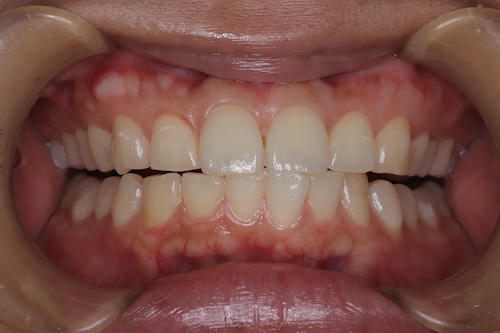

ホワイトニング症例報告

東京 ホワイトニングサロンボーテ神田の症例報告主訴2ヶ月後に挙式をするので、白くしたい

シェードの変化

右上1 A1からBL4

右下3 A3からC1

右上1 B1からBL4

右下3 C1からD2

シェードご満足いただき、メンテへ。

上下の色の差は残りますが、ご本人様ご満足いただけたのでメンテに移行した。